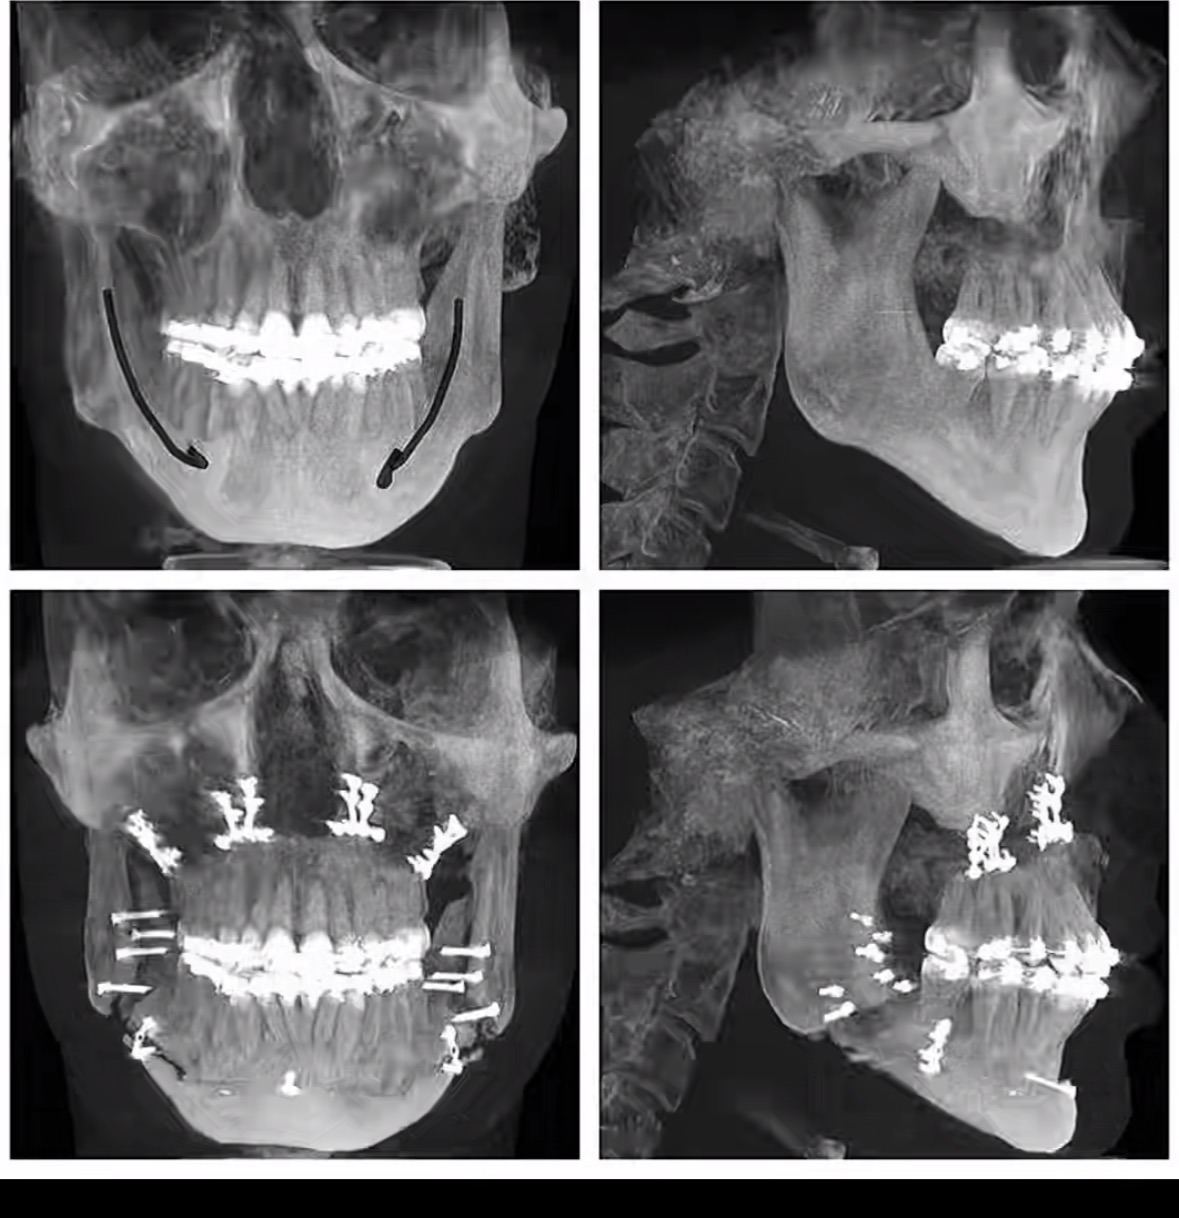

1. Bimaxillary Advancement (Bimax)

Top-tier skeletal hardmaxx.

What it addresses:

- Midface retrusion

- Weak jaw projection

- Poor facial balance

- Airway issues (often medical + aesthetic)

- Stronger jaw

- Better facial harmony

- Improved side profile

- Can be transformative if correctly indicated

Results: